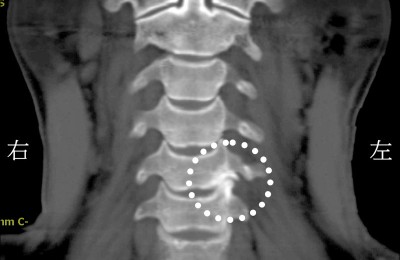

后脑“嗡嗡嗡”声不止?台湾耳鸣晕眩权威揭示颈椎压迫真相

根据中国台湾的媒体报道,台湾高雄有一名40多岁的男性,长期受到肩颈酸痛的困扰,左手前臂常感到麻木和疼痛,甚…